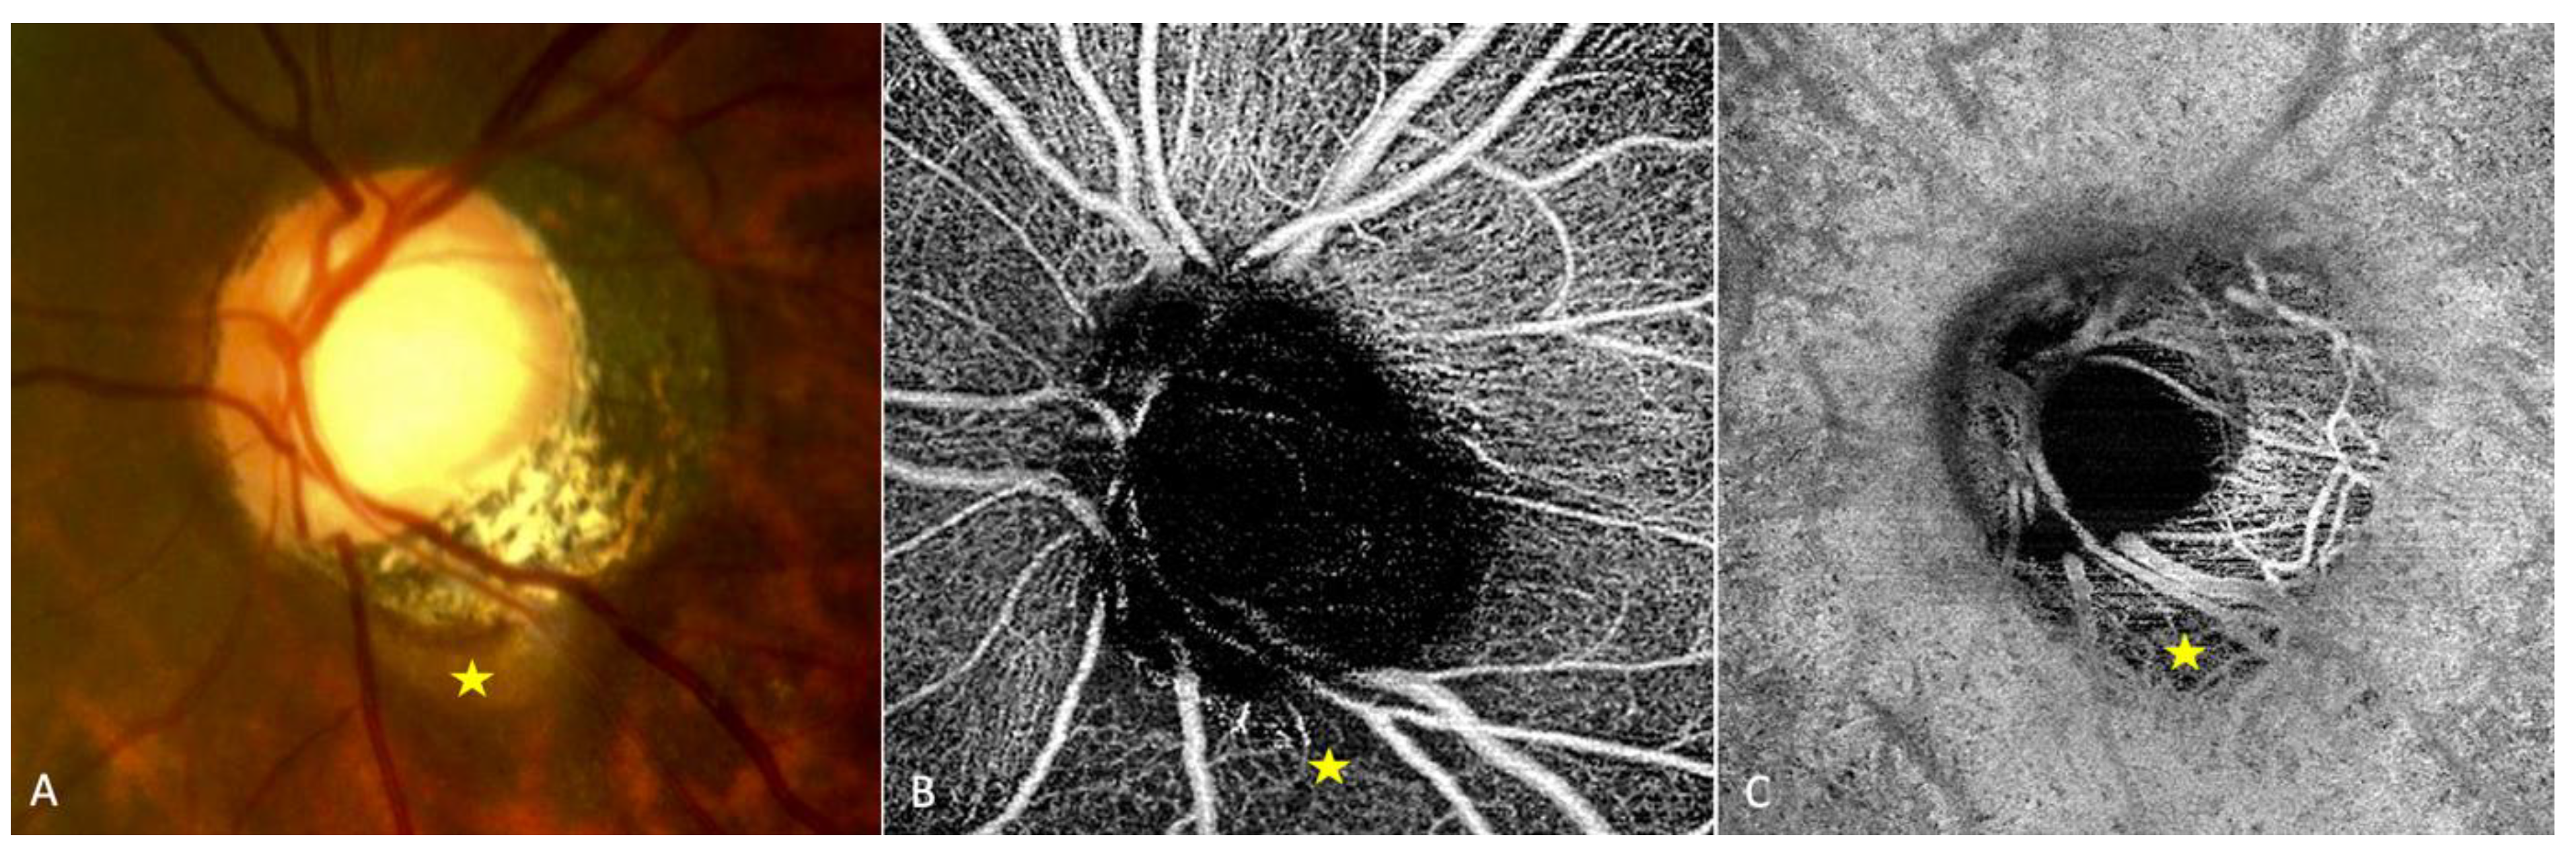

Objective: Multimodal imaging of PICC Design: Case report Examinations: SD-OCT, En-face OCT, ICG, FA, VF |

En-face OCT combined with FA show an early hypo fluorescence resulting from the absence of choroidal tissue and a late staining resulting from the scleral impregnation. | / | Early hypo-fluorescence due to choroidal alteration. Late hyper-fluorescence due to scleral impregnation |